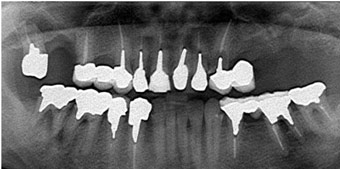

Cさんの上の顎には1本も歯がなく、長年総入れ歯を使っていました。

Cさんの上の顎には1本も歯がなく、長年総入れ歯を使っていました。

Cさんの奥さんは、Cさんほど歯は悪くなかったのですが、部分的に歯を失ってしまいました。Cさんの奥さんは私のところで、インプラント治療を受けて丈夫な歯を歯を手にいれました。そこでCさんは、一大決心をしてインプラントで総入れ歯からの脱出を決意したのです。

Cさんの上の顎は長年の入れ歯生活のせいで、かなり骨が少なくなっていました。

特に前歯の骨は全くないといって状態でした。

特に前歯の骨は全くないといって状態でした。

さらに奥歯はサイナスという空洞が大きくやはり骨がほとんどない状態でした。はっきり言って超難症例です。

Cさんは辛抱強く私の治療についてきてくれました。

骨が少ないので、期間はある程度かかりましたが、その間に私ともスタッフともとても仲良くなって楽しそうに通院していただきました。

奇麗な歯を手に入れたCさんは総入れ歯から脱出をしたのでした。